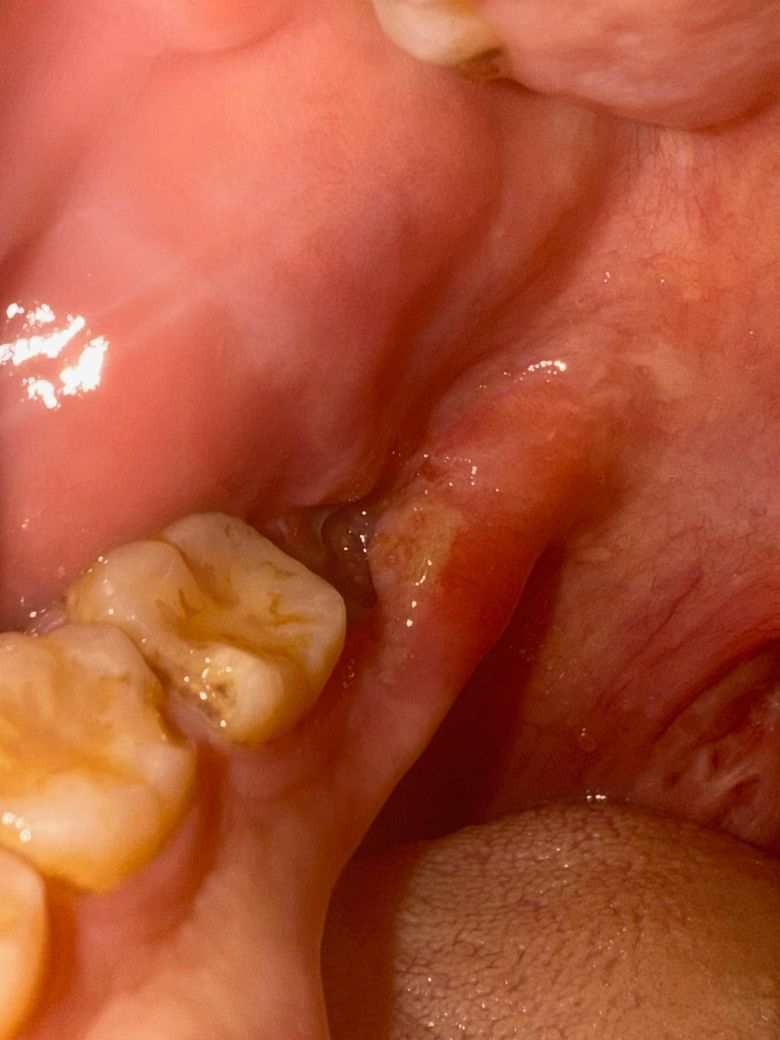

사랑니 발치 3일차, 자고 일어났는데 약간 통증이 있어요

혹시 혈병이 빠지거나 한건가요? 1일차는 좀 통증이 있었고 2일차는 통증 없이 지났는데 3일차인 오늘 일어나니 턱까지 욱신거리는것과 시린 통증이 좀 있네요. 사진상으로도 혈병이 약간 빠진게 아닌가 싶어서 불안합니다.

• 2번 째 사진

사랑니 발치 후에는 일주일 정도 까지는 통증이 느껴질 수 있습니다. 사진상 별 문제 없어보입니다.

사진상으로는 지혈도 잘되신거 같습니다. 아직 상처가 다 아물지 않아서 자극이 가게되면 통증이 생길수도 있습니다.

사진으로 봤을 경우에는 혈병이 제거된 것으로 보이진 않습니다. 발치를 하고 나면 발치한 부위에 상처가 있기 때문에 통증이 있을 수 있습니다. 이런 경우 발치한 부위를 자극하지 않는다면 통증이 점차 줄어들게 됩니다.